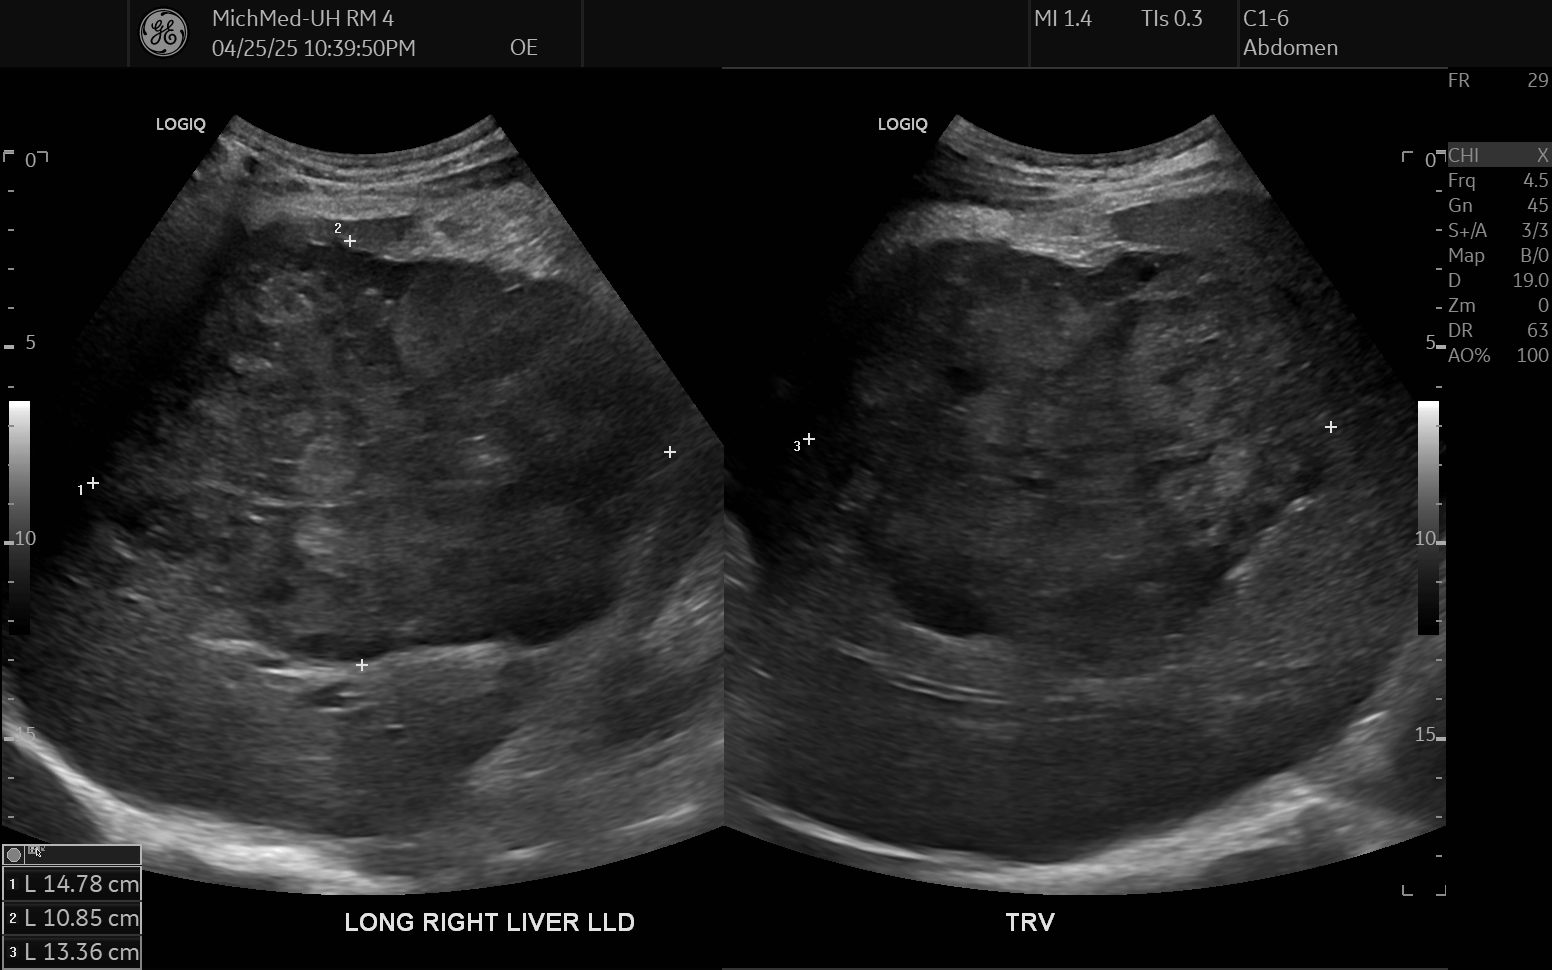

69 M with PMH of HCV cirrhosis & HCC s/p resection in 14 years ago presenting today for a screening ultrasound.

135/73 mmHg / 78 bpm / 16 breaths/min / 96.4°F

sclerae anicteric, no jaundice

CMP wnl, AFP 5